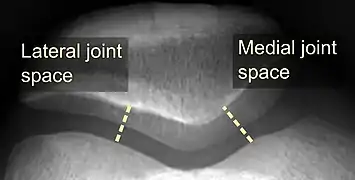

On X-ray, with skyline projections, dislocations are readily diagnosed. In borderline cases of subluxation, the following measurements can be helpful:

- The lateral patellofemoral angle, formed by:[16]

- A line connecting the most anterior points of the medial and lateral facets of the trochlea.

- A tangent to the lateral facet of the patella.

- With the knee in 20° flexed, this angle should normally open laterally.[16]

- The patellofemoral index is the ratio between the thickness of the medial joint space and the lateral joint space (L). With the knee 20° flexed, it should measure 1.6 or less.[16]